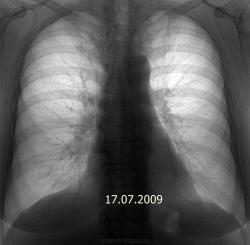

А по снимку от 17.07.09. - показалась гиперплазия правого корня, особенно настораживает тело. В паренхиме - пусто. А вообще, приходится встречаться с такими случаями бурно растущих опухолей, что промежуток в 6 месяцев между флюорографиями пациента не спасает: вот он был (корни не расширены, малоструктурны, паренхима интактна) и вот он пришел (центральный рак, выпирающий по контуру корня с лучистостью и гиповентиляцией верхней доли; на ФБС - карциноматоз трахеи и бронхов, обтурация в\д бронха серой опухолью, цитология - аденокарцинома), а вот через 2 недели его уж и нет на свете (онко:-лечение симптоматическое по месту жительства). Рентгенолог всегда должен быть готов отстоять сою правоту в том, в чем прав.

А по снимку от 17.07.09. - показалась гиперплазия правого корня, особенно настораживает тело. В паренхиме - пусто.